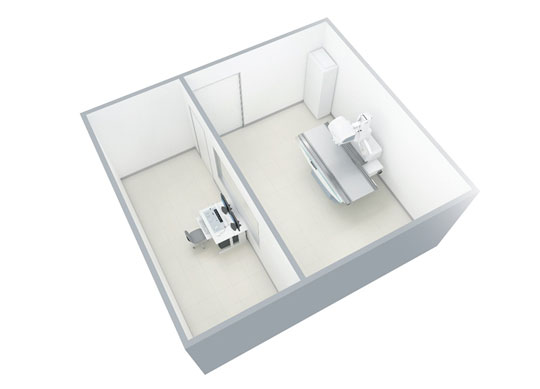

数字化透视摄影X射线机 Neo-Vision

图片内容包含选配组件

Neo-Vision 是一款数字化透视摄影X射线机,可以完成透视检查、摄影检查及连续摄影检查。岛屿式遥控床体、定制化采集方案、无线动态平板探测器满足多种检查应用。